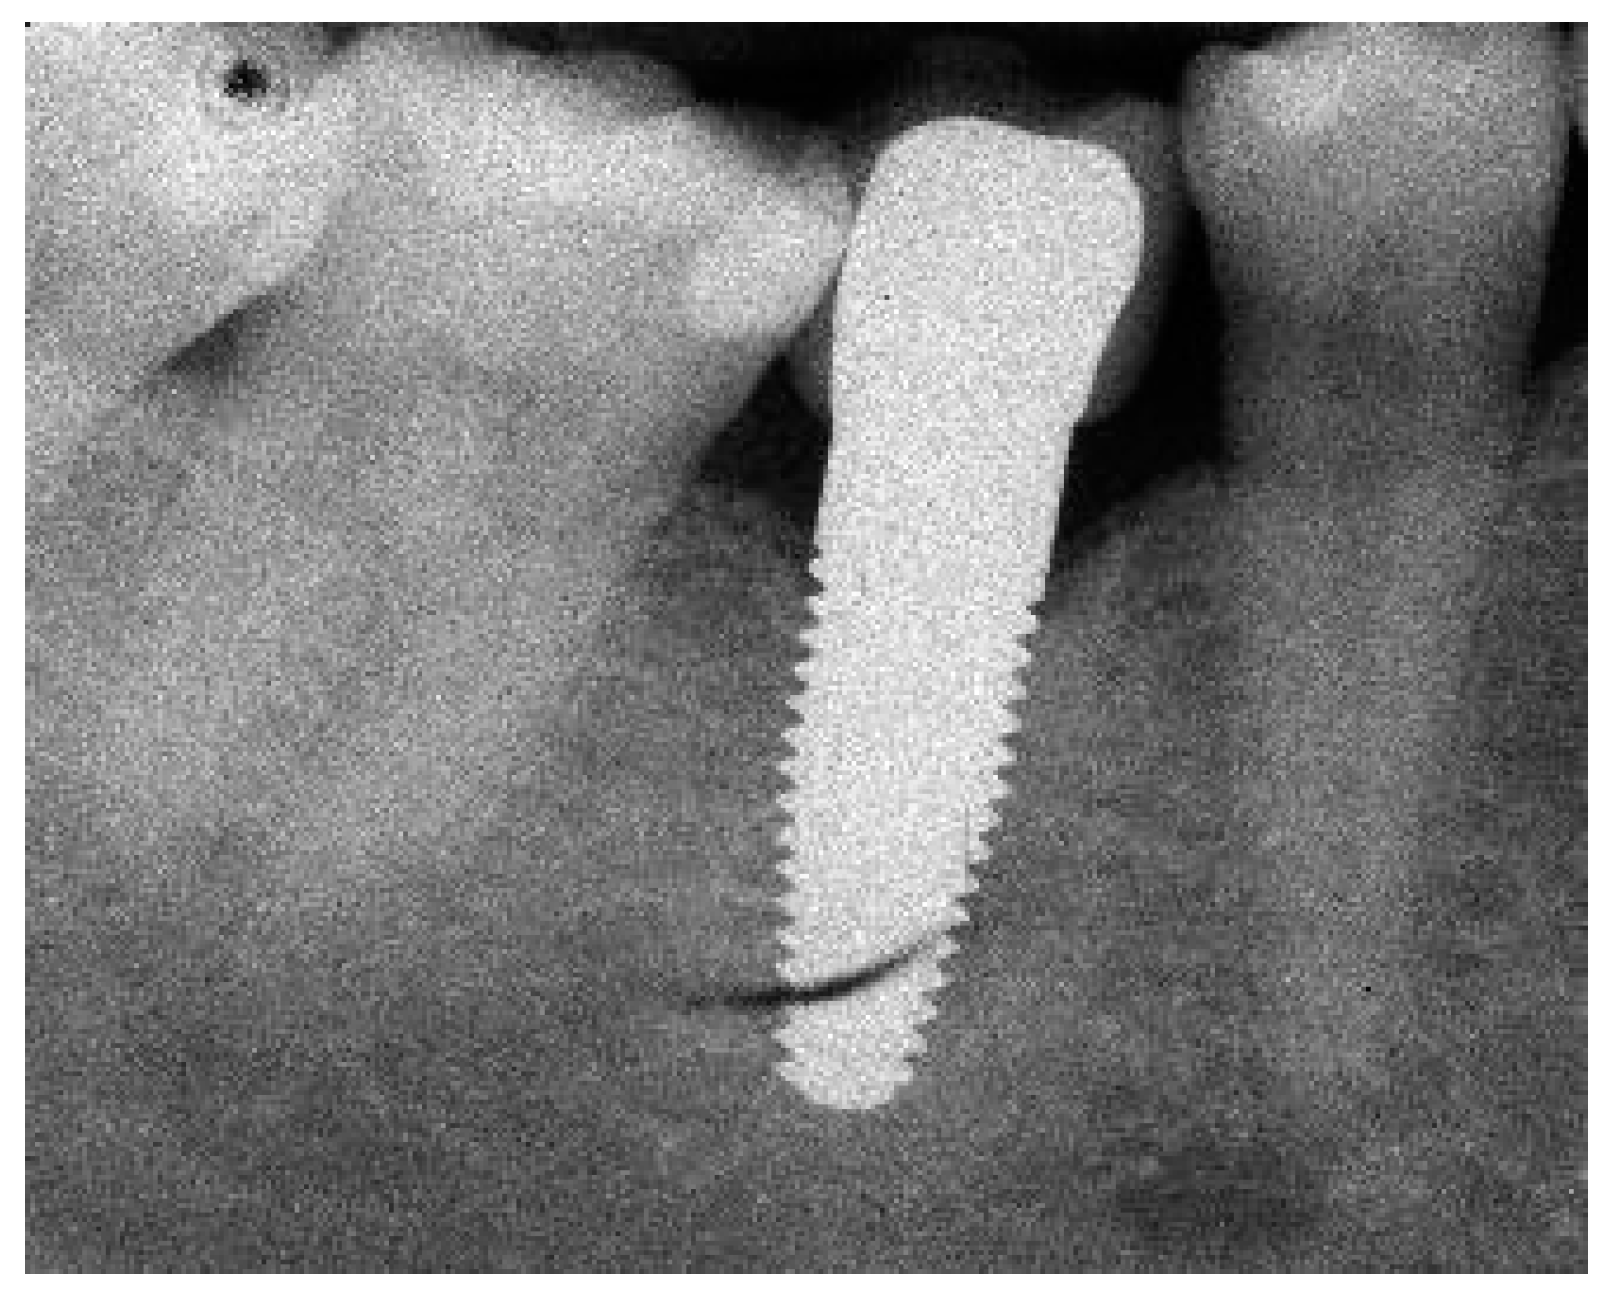

Appendix A. Exemplary Photographs and Radiographs from a Patient at Different Examination Time Points and a Positive Outcome

Appendix B. Exemplary Photographs and Radiographs from a Patient at Different Examination Time Points and a More Negative Outcome